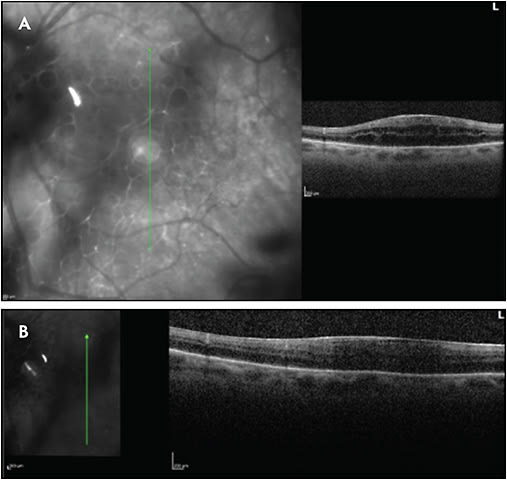

Other complications include glaucoma, posterior synechiae, cataract, epiretinal membrane, vitreous hemorrhage, retinal periphlebitis, retinal neovascularization, macular edema, subretinal fluid, and traction retinal detachment. Glaucoma and cataract, of course, may also be secondary to corticosteroid therapy in the treatment of uveitis. Figures 1-5 show examples of some of these sequelae of MS-associated uveitis. While macular edema in MS is usually secondary to uveitis, or occasionally to the use of fingolimod,33,34 Gelfand35 found that 15 of 318 (4.7%) patients with MS had microcystic retinal edema with no other risk factors, such as uveitis or retinal vascular occlusion. In addition, patients with macular edema had worse vision, worse disability scores, and higher MS severity scores than patients without macular edema. The edema was more common in patients with prior episodes of optic neuritis.

Uveitic CME may fail to respond to immunosuppressive therapy.62 In such cases, topical difluprednate 0.05%, periocular triamcinolone acetonide, and intravitreal corticosteroid therapy such as the dexamethasone implant may be effective.63,64 Overall, the visual prognosis of patients with uveitis and MS is good compared to patients with idiopathic intermediate uveitis. Messenger et al23 found no statistically significant difference between patients with MS and intermediate uveitis and those with idiopathic intermediate uveitis.

Proper treatment of uveitic-associated complications, such as cataract and glaucoma surgery or pars plana vitrectomy with epiretinal membrane, is essential in maximizing long-term visual outcomes. Towler and Lightman30 reported a median visual improvement with cataract surgery or vitrectomy of 3 Snellen lines to a median visual acuity of 6/18. As with other forms of uveitic cataract, it is recommended that uveitis and macular edema be suppressed for at least several months prior to cataract surgery. Perioperative oral steroids65 or the intravitreal dexamethasone implant within 4 weeks before surgery66 are recommended. Occlusive retinal vasculitis with ischemia and retinal neovascularization should be treated with panretinal laser photocoagulation to help prevent vitreous hemorrhage, and pars plana vitrectomy is helpful if hemorrhage occurs.30